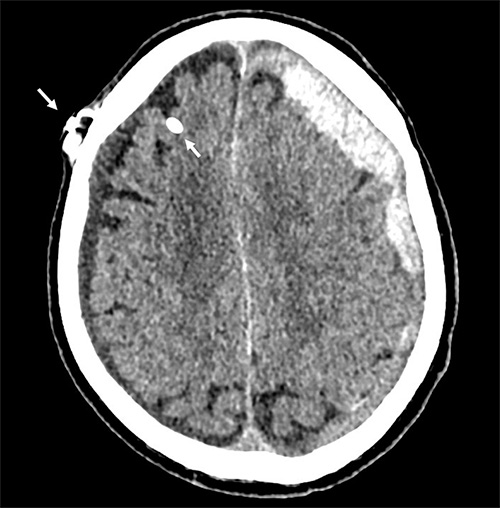

Axial DT-bild av en patient med bilaterala kroniska subduralhematom som uppstått till följd av överdränage. Den vita pricken frontalt höger (pil) utgörs av den röntgentäta intrakraniella katetern.